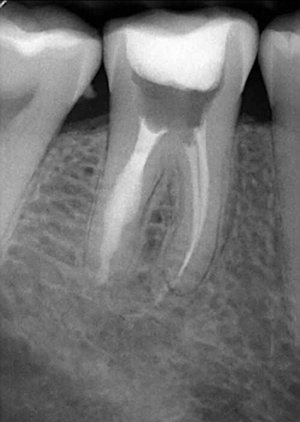

牙體吸收可分為生理性吸收和病理性吸收。如成熟乳牙的牙根吸收,即為一個生理性過程。病理性牙體吸收則包括牙外吸收和牙內(nèi)吸收。牙外吸收的發(fā)生通常與根尖周病變、正畸治療和快速生長的腫瘤有關(guān),始發(fā)部位為牙根外表面或牙頸部,吸收過程由外到內(nèi)。而牙內(nèi)吸收也被稱為髓腔內(nèi)吸收,是指正常的牙髓組織肉芽變性,引起髓腔內(nèi)部牙體硬組織吸收,并逐漸向周圍的牙本質(zhì)層進(jìn)展。如果未能得到及時的治療,將可能導(dǎo)致病變恒牙的早失。恒牙牙內(nèi)吸收較為少見,且常無明顯臨床癥狀,多數(shù)病例為行常規(guī)影像學(xué)檢查時發(fā)現(xiàn)。然而,病變早期并無明顯影像學(xué)改變,這使得牙內(nèi)吸收的早期診斷變得更加困難。因此,當(dāng)患牙出現(xiàn)癥狀或者有影像學(xué)改變時,病變往往己發(fā)展至較嚴(yán)重階段,使得治療難度加大,遠(yuǎn)期效果欠佳。[1]

牙內(nèi)吸收通常無明顯癥狀。根據(jù)吸收的類型和原因,主要分為炎癥性吸收和替代性吸收。其中,炎癥性吸收可能繼發(fā)于前期牙本質(zhì)的細(xì)菌感染和創(chuàng)傷,牙本質(zhì)吸收過程的進(jìn)展不伴有吸收區(qū)鄰近部位硬組織的沉積,吸收部位可見大量肉芽組織,典型的影像學(xué)表現(xiàn)為,以根管為中心的橢圓形透光區(qū)。替代性吸收,導(dǎo)致根管內(nèi)牙本質(zhì)缺損的同時,在缺損區(qū)某些部位還伴有骨樣組織的沉積,造成牙髓腔不規(guī)則的擴(kuò)大和根管連續(xù)性的破壞。根據(jù)牙內(nèi)吸收發(fā)生部位和嚴(yán)重程度的不同,又可呈現(xiàn)不同的征象。若吸收部位發(fā)展至牙冠,可以觀察到牙冠上出現(xiàn)粉紅色的點,這是吸收細(xì)胞鄰近的結(jié)締組織高度血管化的結(jié)果。當(dāng)吸收部位位于根方,則可使得根管原有的形態(tài)缺失,X線片可見根管局部氣球樣的膨大,通常邊界清晰。若牙髓還有部分的活力,則患牙可能有慢性牙髓炎的表現(xiàn);若牙髓完全壞死,則可能發(fā)展成根尖周炎,而出現(xiàn)相應(yīng)的癥狀。竇道的出現(xiàn)往往是己發(fā)生慢性根尖膿腫或根管側(cè)穿的表現(xiàn)。由于患牙冠方的牙髓通常己經(jīng)壞死或被去除,因此敏感性測試常為陰性。